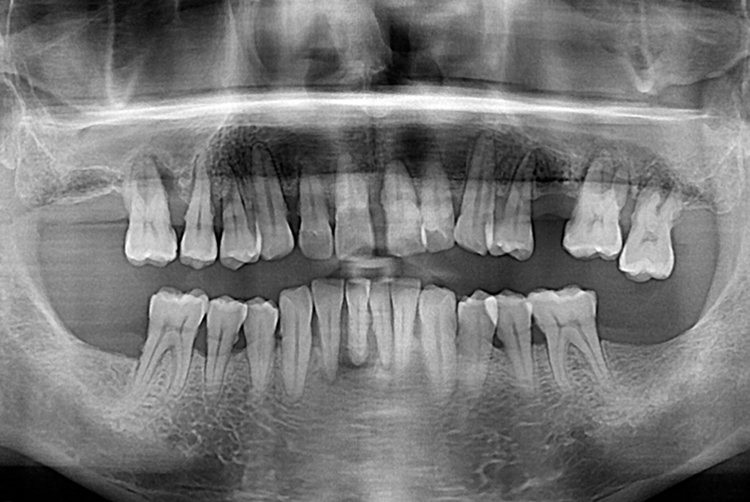

치료전 : 2019-06-12

1500 조현욱_후.jpg

세종치과는 많은 환자와 다양한 케이스를 바탕으로 항상 편안한 임플란트 수술을 제공하고자 노력하고,

오래동안 튼튼히 쓸 수 있는 임플란트 수술을 가장 큰 목표로 삼고 있습니다